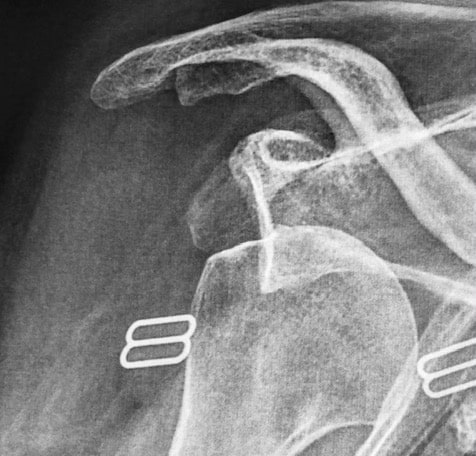

Acromio-claviculaire normale

Disjonction acromio-claviculaire

Stabilisation d'une disjonction acromioclaviculaire

Radio post stabilisation acromioclaviculaire arthroscopique